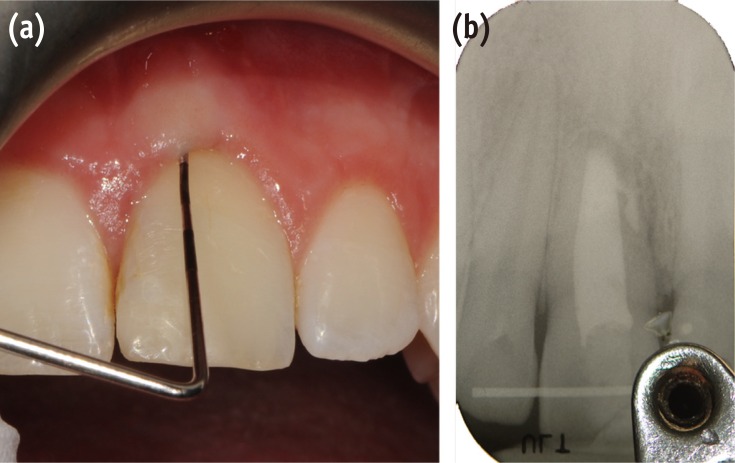

A clinical examination showed a moderate swelling on the vestibular side in the region of tooth #21, as well as the presence of a sinus tract in the same area, approximately 4 mm from the gingival margin (Figure 1). A narrow periodontal defect 7 mm in depth was present on the buccal side, as evaluated using a periodontal probe. A radiographic examination performed before surgery using both periapical radiographs and CBCT (J. Morita MFG Corp., Kyoto, Japan) revealed a root-end resection, a periapical radiolucency, and a widening of the periodontal ligament space at the mesial aspect of the root, although no hair-like fracture line radiolucency was noted in the tooth, except in the CBCT horizontal projection that showed an incomplete VRF 3 mm from the apex (Figure 2).